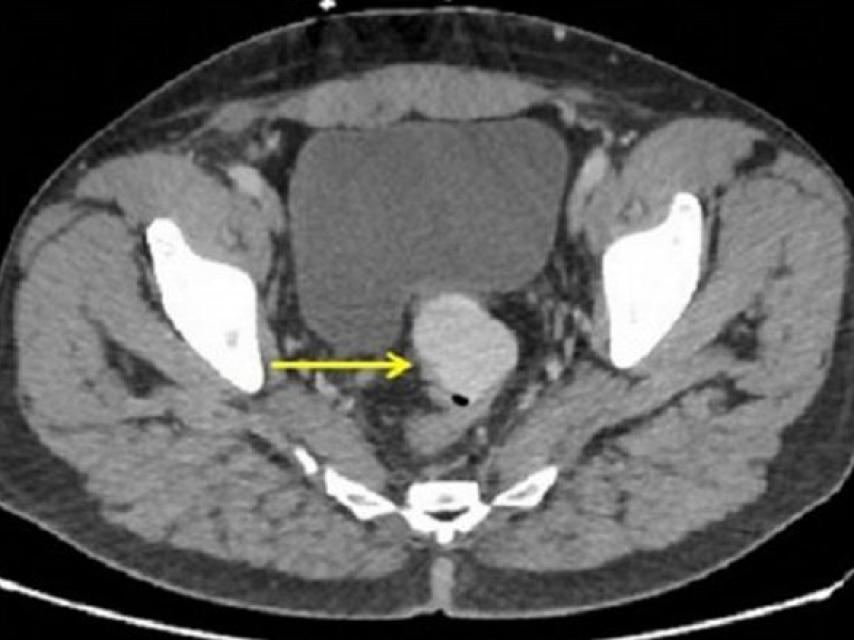

El equipo médico dirigido por el doctor Saad Ikram decidió entonces hacerle una radiografía que hizo saltar todas las alarmas. La placa mostraba una preocupante sombra en el lado derecho de su abdomen. Fue entonces cuando el paciente confesó el tamaño del juguete utilizado, de casi un metro de longitud. Las siguientes exploraciones que se le realizaron revelaron que la práctica sexual había llegado demasiado lejos, se había perforado el intestino y había atravesado todo el abdomen, llegando casi al diafragma.

Radiografía que muestra la perforación en el intestino grueso.